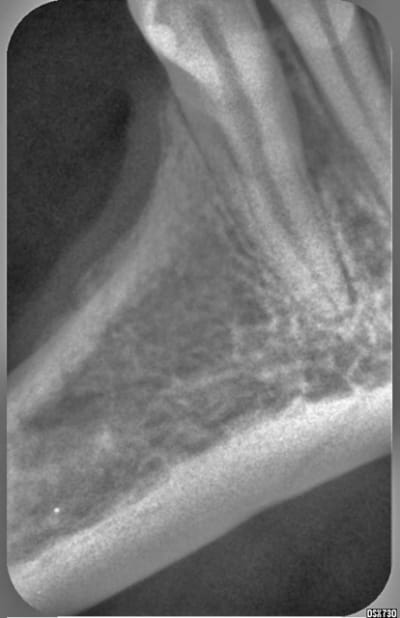

Images eb1m5g - Eugenol

j'ai eu un cas avec une lésion très très similaire sur une 45 mais qui était support de bridge fait par une consoeur.

Malgré la reprise de traitement, l'abcès a récidivé. Il se fistulisait pile au milieu de la papille interdentaire. On s'est orienté vers une félure horizontale car absence de sondage positif.

Il ne faut pas oublier que la fracture est une étiologie possible dans les cas de descellement prothétique.

Je pencherais donc pour cette hypothése. D'autant plus que cette dent amortit des contraintes occlusales majorées par l'édentement dital.

Je m'orienterai vers un lambeau d'exploration avant de faire quelque chose.

une deuxieme racine?